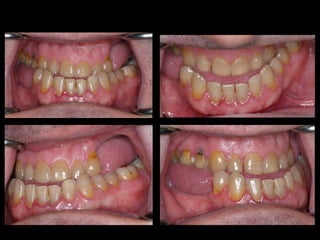

Anquilosis ATM Hiperplasia condílea Cirugía ortognática

Modelos estereolitográficos  SAHS moderado Hipoplasia maxilar

Anquilosis ATM Hiperplasiacondílea Cirugía ortognática